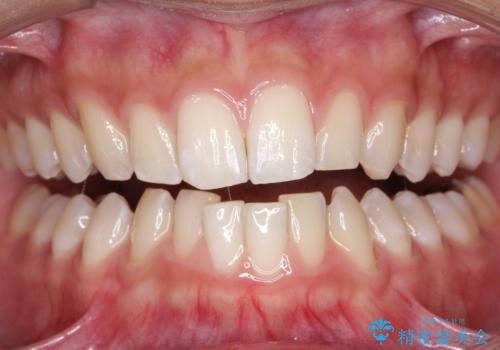

矯正治療中も歯の黄ばみをきれいにしたい

担当医 歯科衛生士